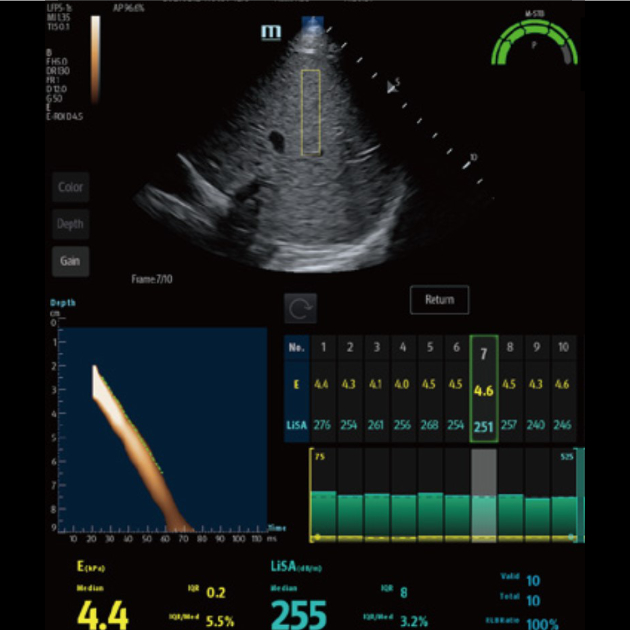

Hepatus ist ein professionelles, nicht-invasives Diagnosesystem bei Verdacht auf Lebererkrankungen und liefert quantitative Ergebnisse, die das Stadium von Leberfibrose anzeigen. Es ist genau, effizient und verl?sslich und kann nach einer Erkrankung sehr bequem f├╝r Nachsorgeuntersuchungen eingesetzt werden. Damit st??t es die T├╝r zu einer neuen ?ra der Diagnose von Lebererkrankungen auf.

Zahlreiche Ultraschall-L?sungen*

┬и Professionelle Ultraschallsonde zur Erleichterung der Untersuchung von Aszites usw.

┬и Spezielle, ultraschallgesteuerte Punktion zur Erh?hung der Genauigkeit der Biopsie

┬и Exzellentes Ultraschallbild und ebensolche Ultraschallfunktion erm?glichen umfassende Bewertung von Lebermorphologie und H?modynamik.